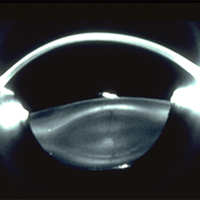

Rush is one of the few academic programs to have implemented a separate section of refractive surgery with a strong commitment and emphasis on resident education. The Eye Center has an on-site state-of-the-art wavefront guided excimer laser and femto-second laser. Second- and third-year residents rotate on the refractive surgery service and actively participate in the screening program, surgery and postoperative management. Residents are expected to become proficient in PRK and LASIK for a variety of myopic, hyperopic and astigmatic refractive errors. Complex cases due to keratoconus, and corneal thickness abnormalities are managed. Collagen corneal cross-linking is available to appropriate patient. Additionally, residents all gain experience in refractive cataract surgery and become comfortable using a variety of astigmatism and presbyopia correcting intraocular lenses throughout their third year of training. Morning refractive surgery rounds enhance the training. By the end of training, residents are able to implement refractive surgery into their practice. The Refractive Surgery Section faculty who participate in the resident continuity clinic include Section Director Jonathan B. Rubenstein, MD, Parag A. Majmudar, MD, Anjali Tannan, MD, and Vanee Virasch, MD.